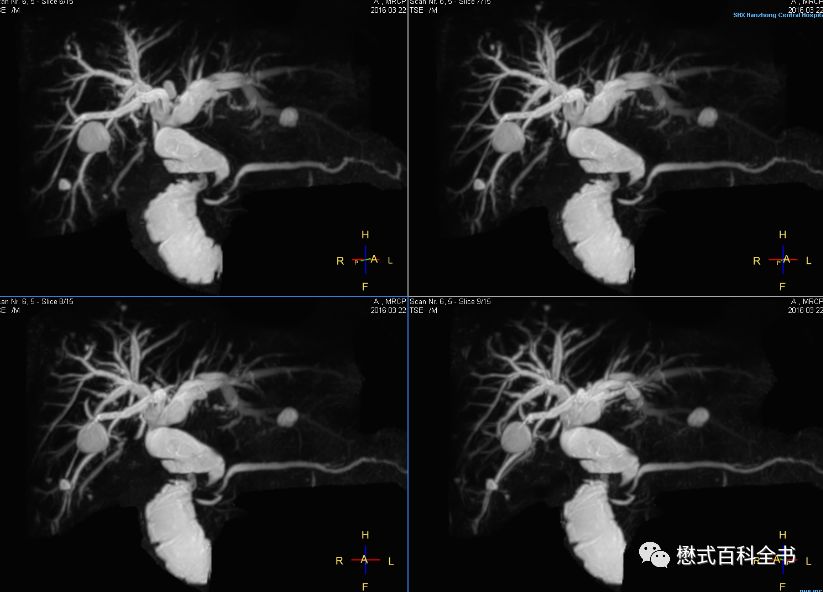

图21:3D MRCP扫描

如图,3D MRCP扫描,容积采集后,然后做MIP(最大信号强度投影重建)。

3D MRCP优点是:信噪比高,可以出薄层图像,而且可以通过图像后处理MIP形成胆管树形结构图,这种图临床医生非常喜欢看,对胆管系统整体结构显示清晰。

但是,3D MRCP也有致命的缺点,如图,如果没有经验的影像医生或者临床医生只看重建的MIP图,而不看原始的薄层图像,则容易出现假阴性(由于最大信号强度投影的图像后处理算法关系,有可能把本来的充盈缺损,显示结石的给遮掩了)。本来有结石的,结果做了MIP后,无法显示充盈缺损了。另外,3D MRCP序列扫描时间也长。